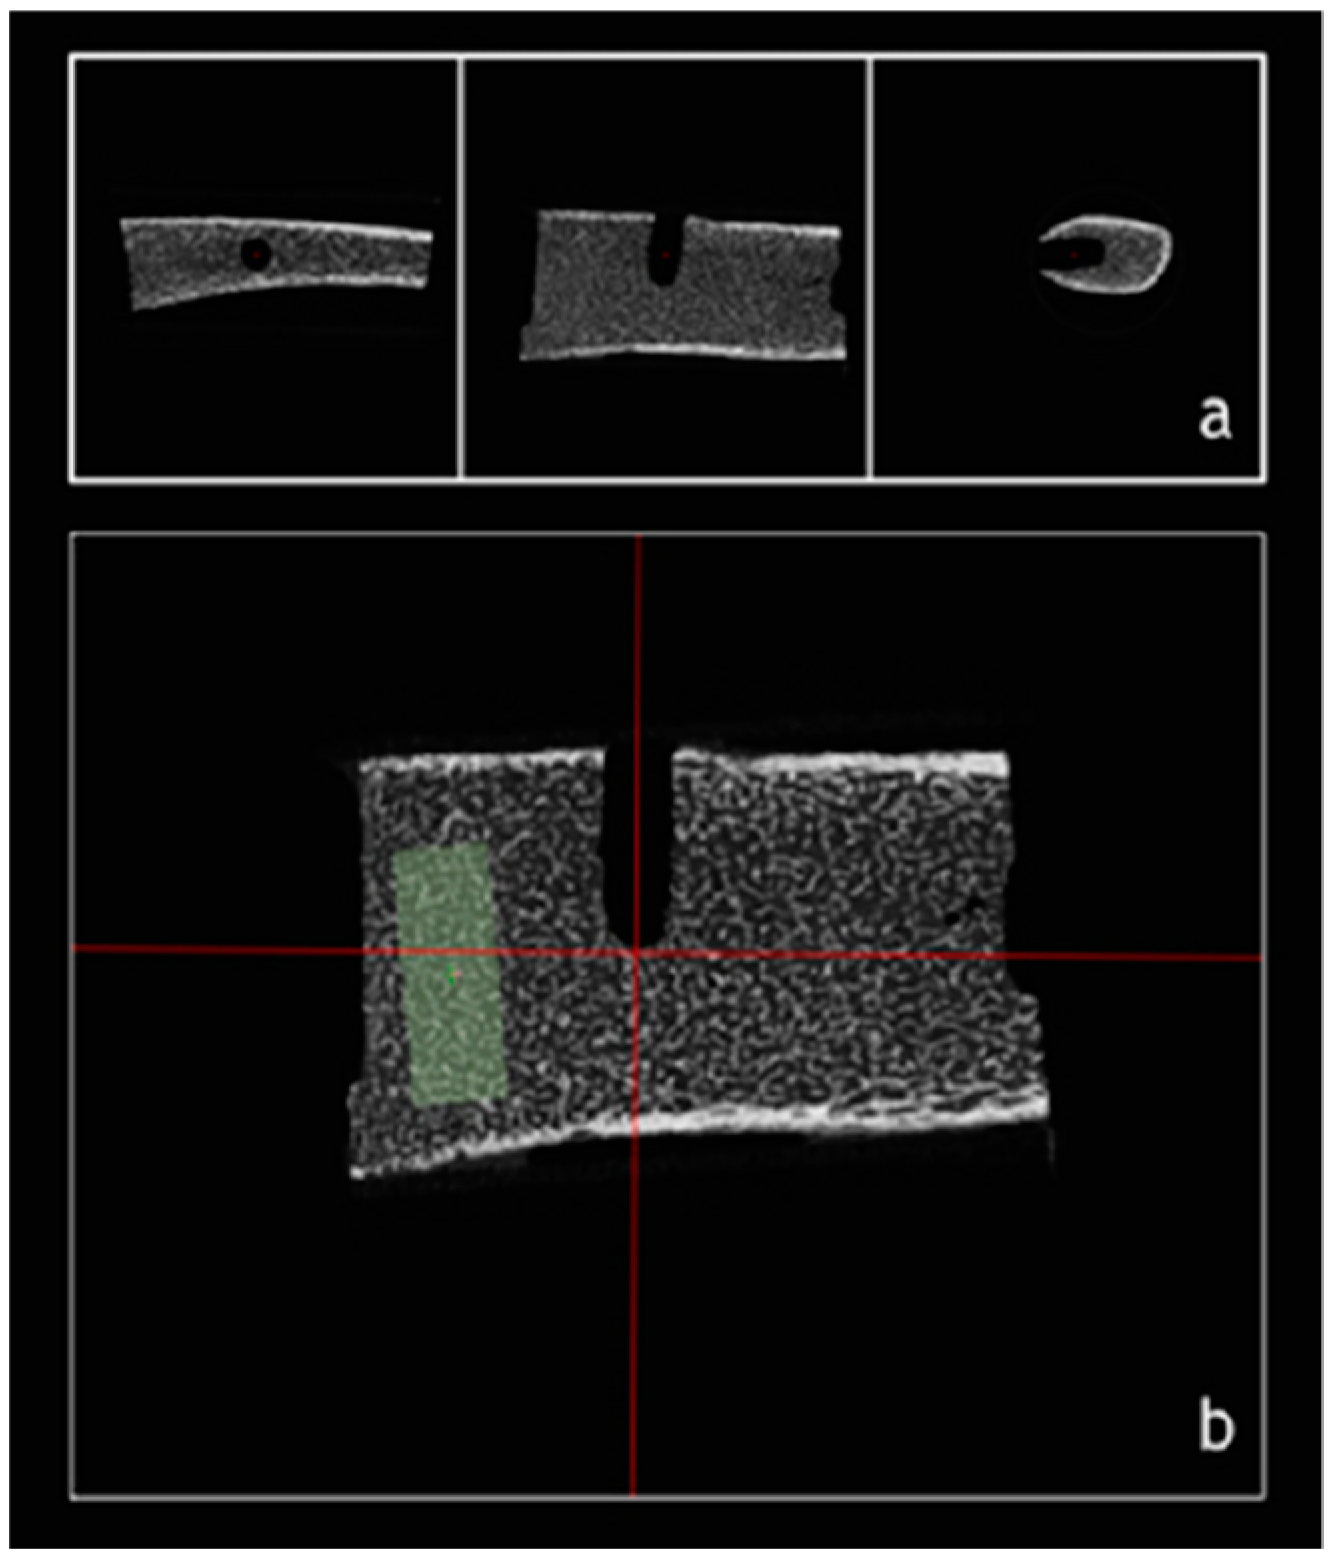

- Gremse, F.; Stärk, M.; Ehling, J.; Menzel, J.R.; Lammers, T.; Kiessling, F. Imalytics Preclinical: Interactive Analysis of Biomedical Volume Data. Theranostics 2016, 6, 328–341. [Google Scholar] [CrossRef] [PubMed]